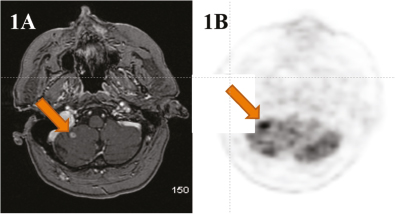

Fig 4

Figure 4. Tumor monitoring. 18F-FET PET correctly indicates the presence of tumor recurrence verified by histology, (4A) and the absence of tumor recurrence, verified by clinical follow up, (4B) whereas MRI is equivocal for tumor recurrence versus radionecrosis after treatment with radiotherapy or radiosurgery for metastatic lung cancer in the brain. (Courtesy of Karl-Josef Langen, Department of Nuclear Medicine, RWTH University Clinic and Research Center Jülich, Germany).